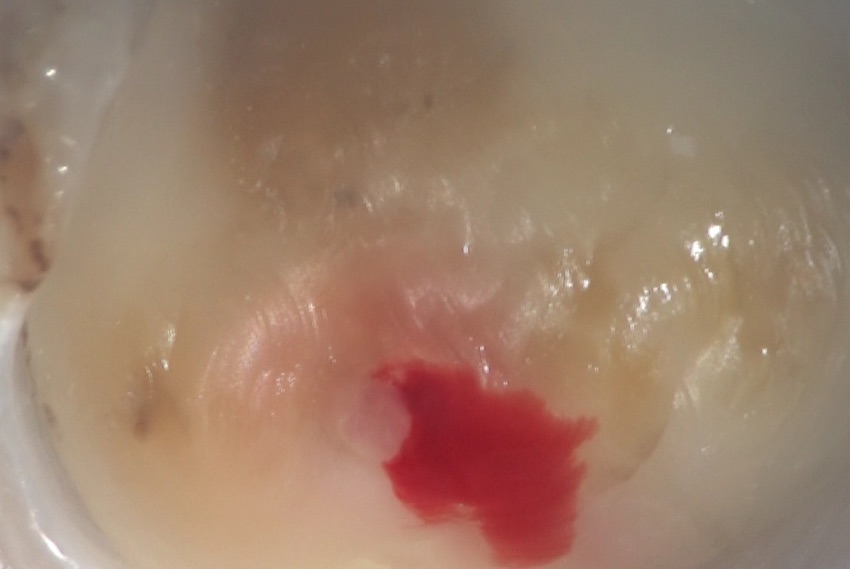

このあと、歯の内部にアプローチ、いわゆる根管治療を行うために、歯に穴を開けていきます。

これが、歯髄と呼ばれる軟組織、いわゆる神経、と呼ばれているものです。

この神経を洗い流し、この軟組織の入っている部分のその上の部分取り除いた部分です。左右に見えるのが、神経の管、つまり根管の入り口です。